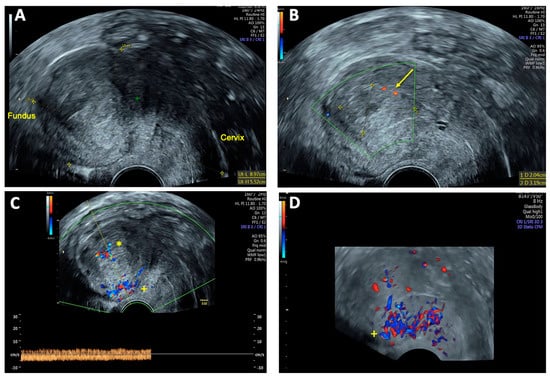

On vaginal examination, no abnormalities or active bleeding were observed. Transvaginal ultrasound revealed a retroflexed uterus measuring 81 × 51 mm, with a suspicious, irregular, hypoechoic, hypervascular lesion measuring 40 × 34 mm on the posterolateral wall of the uterus. This lesion appeared as a prominent vascular tangle extending toward the uterine cavity. Color Doppler sonography demonstrated high-velocity blood flow within the lesion, with a peak systolic velocity (PSV) of 0.3 m/s and a low-resistance pattern, indicated by a resistance index (RI) of 0.43. Distinct arterial and venous blood flow patterns were clearly visualized within the suspicious area (Figure 1 and Figure 2). Both ovaries exhibited normal physiological morphology, appearance, size, and follicle count without abnormalities.

Figure 1. Transvaginal sonography (TVS) Imaging of uterine arteriovenous malformation (AVM): (A) 2D TVS demonstrating a retroflected, enlarged uterus measuring 81 × 51 mm with an inhomogeneous structure in the uterine cavity and fundus; (B) 2D TVS with color Doppler revealing a vascular tangle suggestive of an AVM (arrow); (C) 2D TVS with color Doppler illustrating arterial blood flow within the lesion; (D) 2D TVS with color Doppler depicting venous blood flow in the affected area.